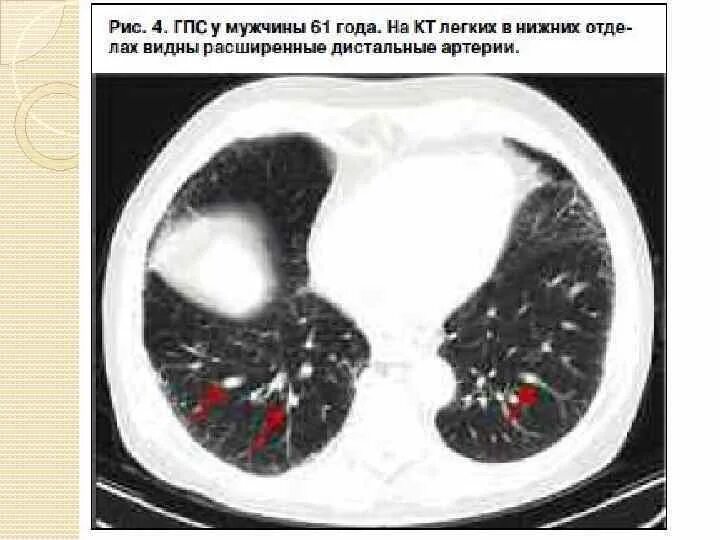

Цирроз на кт